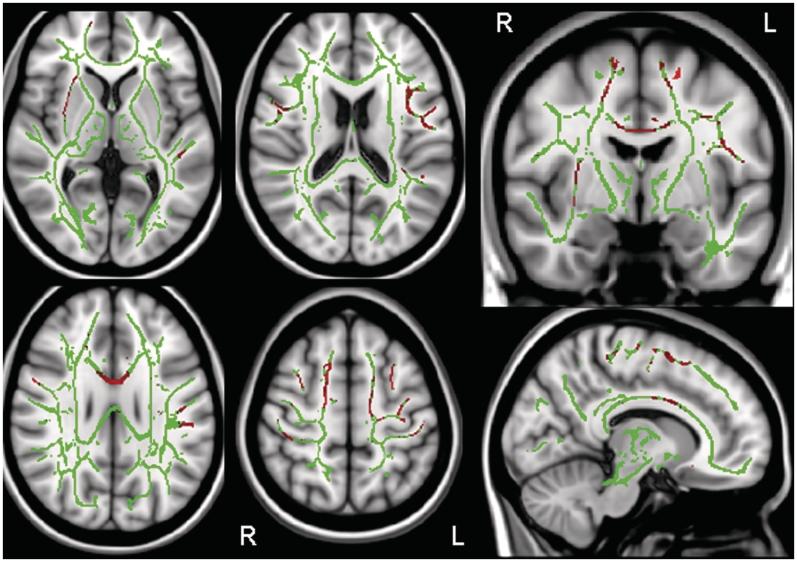

Apraxia of speech is a disorder of speech motor planning and/or programming that is distinguishable from aphasia and dysarthria. It most commonly results from vascular insults but can occur in degenerative diseases where it has typically been subsumed under aphasia, or it occurs in the context of more widespread neurodegeneration. The aim of this study was to determine whether apraxia of speech can present as an isolated sign of neurodegenerative disease. Between July 2010 and July 2011, 37 subjects with a neurodegenerative speech and language disorder were prospectively recruited and underwent detailed speech and language, neurological, neuropsychological and neuroimaging testing. The neuroimaging battery included 3.0 tesla volumetric head magnetic resonance imaging, [(18)F]-fluorodeoxyglucose and [(11)C] Pittsburg compound B positron emission tomography scanning. Twelve subjects were identified as having apraxia of speech without any signs of aphasia based on a comprehensive battery of language tests; hence, none met criteria for primary progressive aphasia. These subjects with primary progressive apraxia of speech included eight females and four males, with a mean age of onset of 73 years (range: 49-82). There were no specific additional shared patterns of neurological or neuropsychological impairment in the subjects with primary progressive apraxia of speech, but there was individual variability. Some subjects, for example, had mild features of behavioural change, executive dysfunction, limb apraxia or Parkinsonism. Voxel-based morphometry of grey matter revealed focal atrophy of superior lateral premotor cortex and supplementary motor area. Voxel-based morphometry of white matter showed volume loss in these same regions but with extension of loss involving the inferior premotor cortex and body of the corpus callosum. These same areas of white matter loss were observed with diffusion tensor imaging analysis, which also demonstrated reduced fractional anisotropy and increased mean diffusivity of the superior longitudinal fasciculus, particularly the premotor components. Statistical parametric mapping of the [(18)F]-fluorodeoxyglucose positron emission tomography scans revealed focal hypometabolism of superior lateral premotor cortex and supplementary motor area, although there was some variability across subjects noted with CortexID analysis. [(11)C]-Pittsburg compound B positron emission tomography binding was increased in only one of the 12 subjects, although it was unclear whether the increase was actually related to the primary progressive apraxia of speech. A syndrome characterized by progressive pure apraxia of speech clearly exists, with a neuroanatomic correlate of superior lateral premotor and supplementary motor atrophy, making this syndrome distinct from primary progressive aphasia.